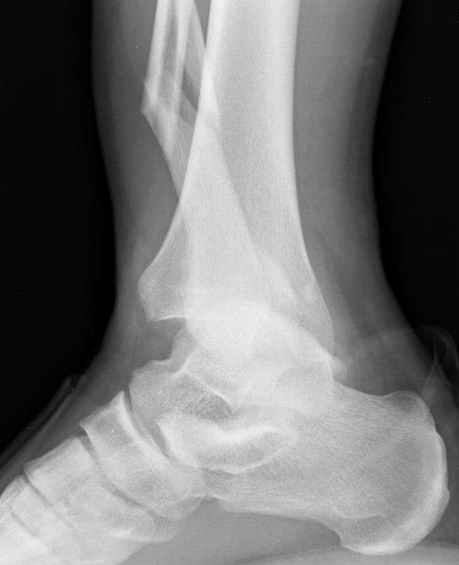

>На сделанных у нас снимках видно, что не все благополучно...

Неравномерность суставной щели может быть связана с разрывом глубокой порции дельтовидной связки и ротацией м/берцовой кости за счет поврежденных структур синдесмоза(репозиция ее на уровне перелома как-будто удовлетворительная).

По моему мнению,ассиметрия суставной щели обусловлена импрессией медиальной части суставной поверхности б/б кости. Да, позиционный винт здесь не лишен, но через 4 недели целесообразность его проведения сомнительна, брейс, ограничение осевой нагрузки достаточно.Есть еще деонтологические аспекты повторной операции, не все так плохо выполнено предыдущим доктором!

Импрессия медиальной части суставной поверхности бывает при супинационном механизме перелома лодыжек (тип А по классификации АО). Здесь механизм пронациия+наружная ротация (тип С, синдесмоз и межкостная мебрана повреждены),

перелом медиальной лодыжки отрывной, при этом в 20-30% бывает повреждение дельтовидной связки.

Клиновидность щели сустава следствие повреждения дельты, невосстановления длины малоберцовой или (хотел сказать "установки в гипсе", но оного, вроде,

нет)? Устранить бы причину. А равно как и тенденцию" к наружному подвывиху. Чрескостный остеосинтез - метод выбора.

Мое мнение, что никакой ротации малоберцовой кости здесь нет и синдесмоз тоже впорядке. Все дело в некачественно репозиции медиального мыщелка. Скорее всего его или немного ротировали при операции или сместили латерально. Более склонен ко второму варианту.

Конечно, компьютерный томограф более информативный метод, но с помощью недорогого обычного стандартного в нейтральном положении стопы: прямого, бокового и косой (ankle mortise) ренгенологического метода можно получить полную информацию о повреждении голеностопного сустава, а сравнительный снимок с другой стороны подтвердить наличие повреждения.

При реконструкции голеностопа, о важности восстановления длины малоберцовой для профилактики пост травматического артроза разбирали в предыдущих дискуссиях. Нарушенную биомеханику голеностопа без восстановления длины малоберцовой, не восстановить только швом медиальной связки.

Расширенная медиальная щель более чем на 4 мм и укорочение малоберцовой более чем 2 мм, а перелом заднего края большеберцовой смещения более 2мм с вовлечением 30% поверхности сустава, считается отходом от нормы голеностопного сустава, и подлежит к оперативному вмещательству.